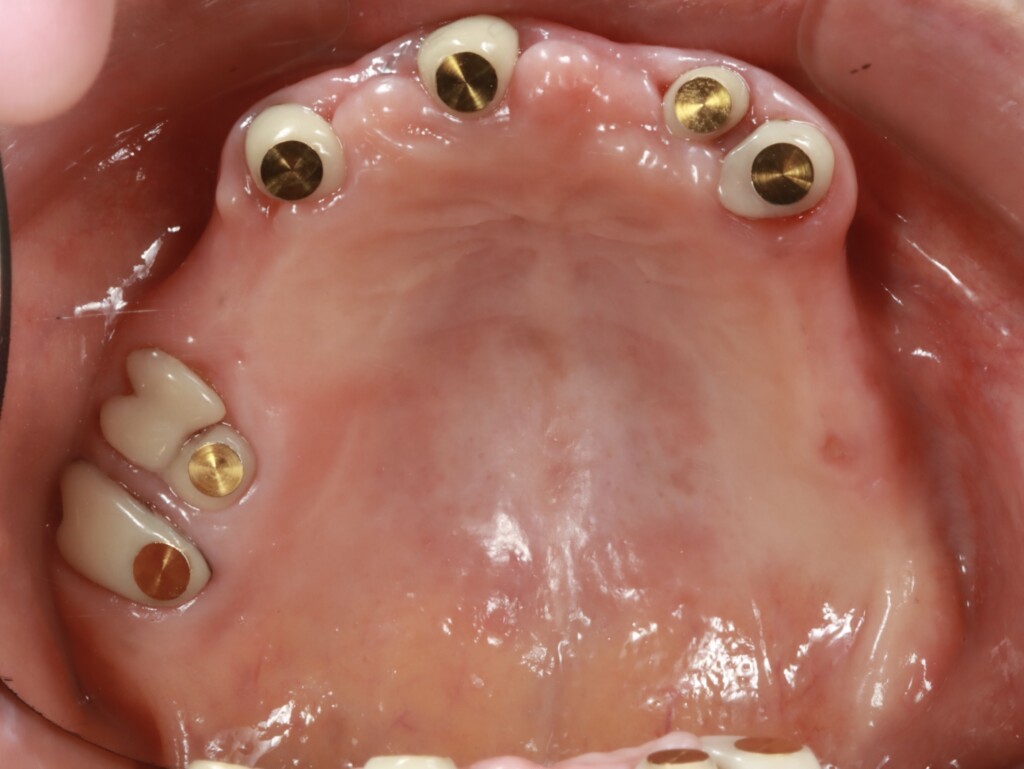

磁性アタッチメントが装着された状態(上顎)

仮歯と仮入れ歯を修理して作った磁石で安定する仮入れ歯

磁性アタッチメントは、歯に引っかけて入れ歯を固定するのではなく、磁石の力でくっつけることで入れ歯を安定させる仕組みです。そのため、硬いものを噛むなど、食事中に横から無理な力がかかった場合でも、歯に負担がかかり続けるのではなく、自然に外れることで力を逃がす構造になっています。一方で、強く固定する構造ではないため、安定感には一定の限界があります。過度な力がかかった際には外れて歯を守る仕組みであるため、状況によっては外れやすいと感じることがあります。また、磁性アタッチメントは、歯の側に装着する「磁性金属(キーパー)」と、義歯の内側に組み込まれる「磁石構造体(マグネット)」で構成されています。磁性金属とは、普段は磁石ではありませんが、磁石が近づくと引き寄せられる性質をもつ金属です。義歯に内蔵される磁石は医療用として安全性が確認されており、お口の中で長期間使用することを前提に設計されています。そのため、通常の使用で体に影響が出ることはほとんどありません。ただし、MRI検査の際には、磁石の影響により、あごや顔まわり(口元付近)の画像が見えにくくなる可能性があります。そのため、事前に医師や検査スタッフへ申告が必要です。検査部位によっては画像に影響が出る場合があるため、状況に応じて義歯の取り外しを検討することがあります。